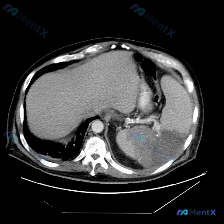

- 定位:上腹部CT软组织窗,左侧脾脏层面

- 关键异常:

- 脾脏肿大;

- 脾实质内见大范围、边界尚清晰但密度不均匀的低密度影,形态呈相对弥漫或片状,主要占据后部及部分中部;

- 其他阴性/参考表现:肝脏实质密度均匀;胃壁无明显增厚;腹膜后、脾门区未见明显肿大淋巴结;腹膜后脂肪间隙清晰,无明显渗出。